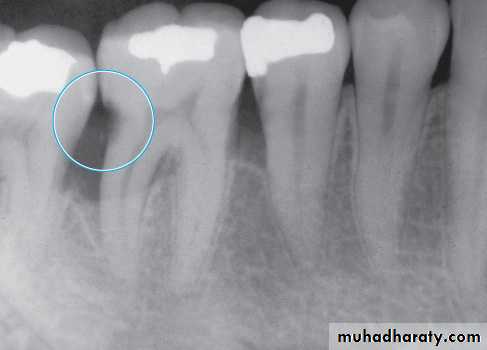

Radiograph of cemental (root) caries. The large radiolucency on the distal surface of the distal root of the first mandibular molar

Dental Root Caries